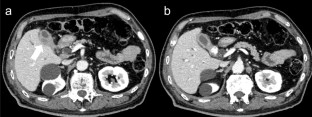

Gallbladder cancer is often diagnosed with metastasis and is known to have poor prognosis. Although, gallbladder cancer often metastasizes to liver, lung, or lymph nodes, metastasis to gastrointestinal tract is not common. Several autopsy studies reported colorectal metastasis from gallbladder cancer, but most of these cases were supposed to be gastrointestinal invasion from peritoneal dissemination. We experienced a rare case of hematogenous colon metastasis from gallbladder cancer. Colonoscopy for a 76-year-old man who was diagnosed as gallbladder cancer revealed two 5-mm flatly elevated lesions with central erosion in the transverse and sigmoid colon. Endoscopic mucosal resection (EMR) revealed poorly differentiated adenocarcinoma in hematoxylin and eosin staining. Additional immunohistochemistry examination showed strongly positive CK7 expression with negative CDX2, and suggested colon metastases from gallbladder cancer. Despite the positive vertical margin in EMR specimens, autopsy finding denied colorectal invasion from peritoneal dissemination and proved vascular spread colon metastases. Gastrointestinal metastasis is often misdiagnosed as a primary tumor, and thus, it is important to recognize gallbladder cancer as a potential origin of gastrointestinal metastasis.

Fig. 2